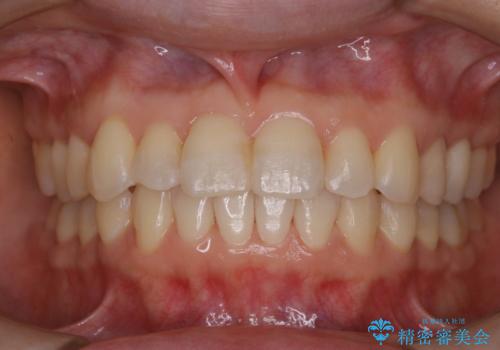

- 久しぶりの来院で歯磨きチェックとクリーニング希望とのことでした。染め出しとPMTC30分コースを行いました。

一見きれいに見える歯でも、染め出し(歯垢染色液)を使うとこのように歯と歯茎の境目や、歯と歯の間などに磨き残しがあることがわかります。歯磨きには、いつも気をつけているから磨き残しはナシと思っていても、実際完璧に磨ききることはなかなか難しいです。歯科医院にて、専門の機械で定期的なPMTCを行うことが大切です。